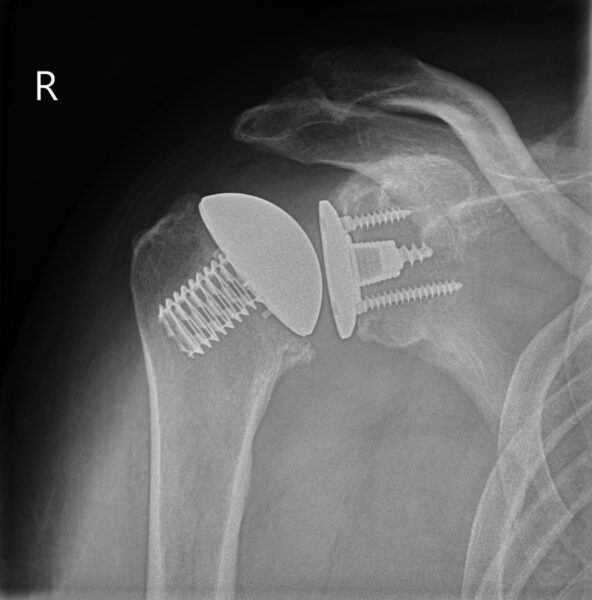

Halve schouderprothese

Een halve schouderprothese heet ook wel een hemi-schouderprothese. Bij een halve schouderprothese vervangen we alleen de schouderkop. Dit kan alleen als de kom van het schouderblad nog goed is.